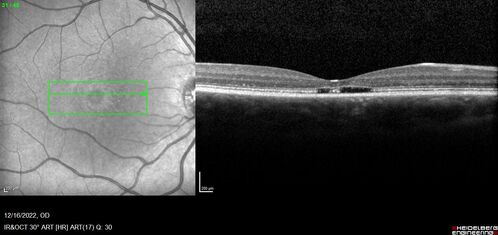

Stargardt Disease - Very Mild - 24 year old

This patient has 3 different ABCA4 mutations. His mother and sister have stargardts and his father has RP. His sisters images are also on Retinagallery.com

Stargardt Sibling - ABCA4 3 mutations